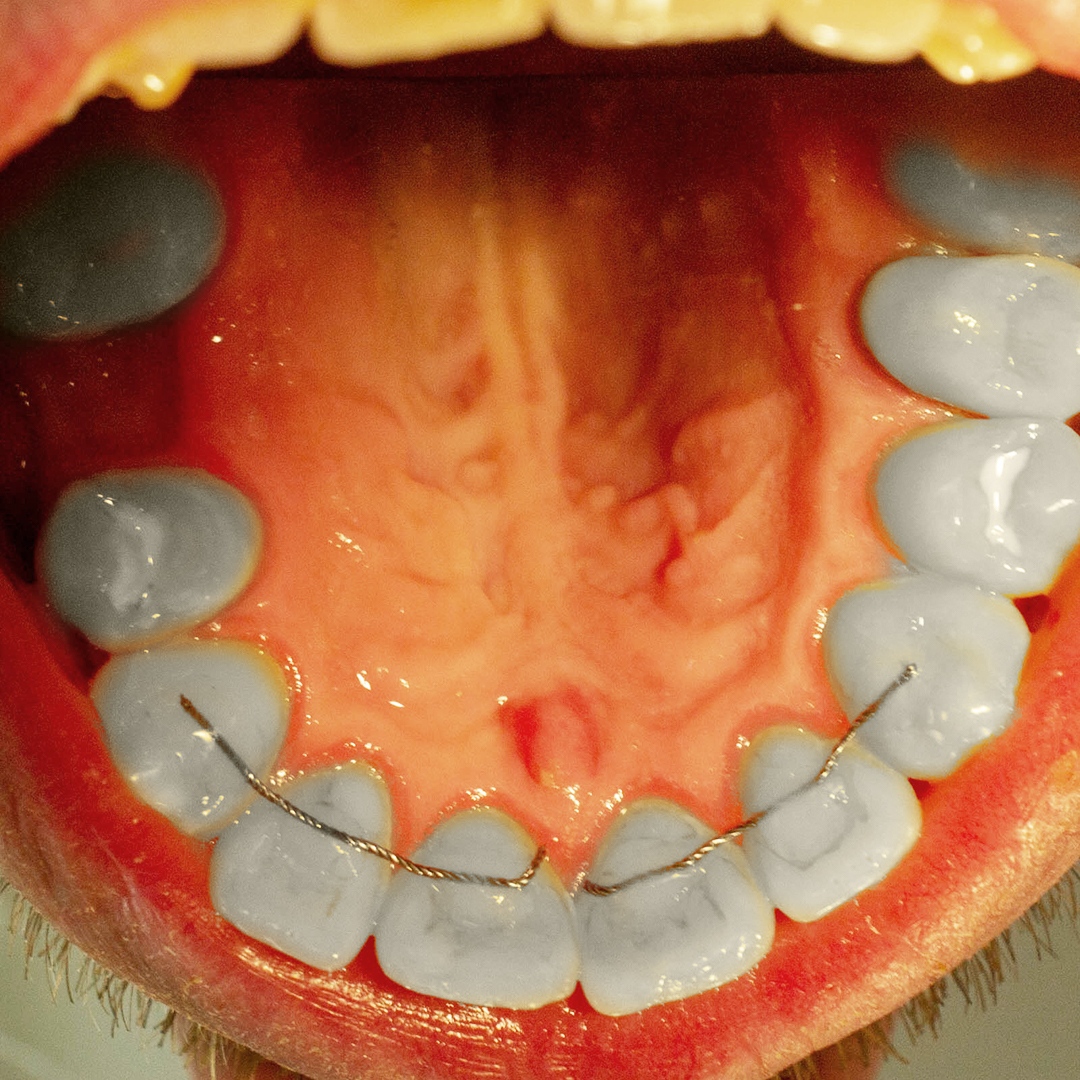

В клинику обратился пациент с жалобами на разрушение зуба 2.5 и застревание пищи между зубами. Врач провёл осмотр, консультацию, назначил проведение анализа КЛКТ. По результатам исследования совместно с пациентом принято решение установки металлокерамической коронки с культевой штифтовой вкладкой.

Протезирование позволяет восстановить эстетику улыбки и функциональность разрушенных зубов без необходимости установки имплантов. Металлокерамические коронки обладают высокой прочностью, комфортны в ношении и прослужат вам в среднем 12-15 лет.